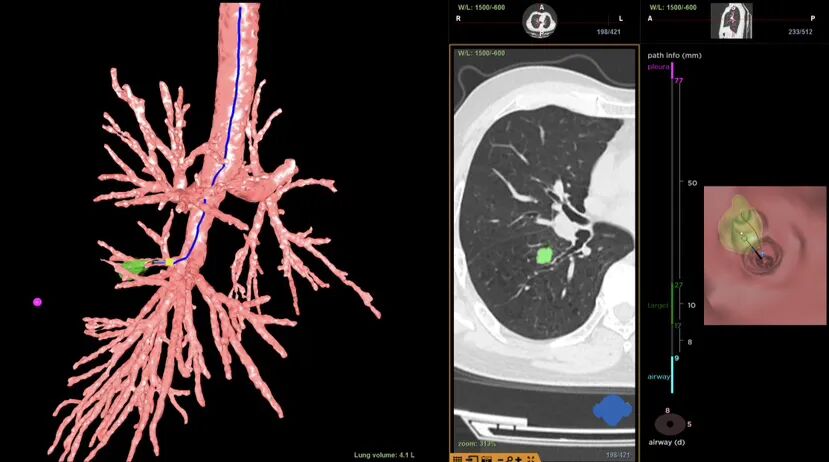

前Lung pro规划路径

术前,团队进行了充分的准备,用气道内的“GPS”虚拟导航系统(Lung pro)规划出抵达病灶的最优路径。